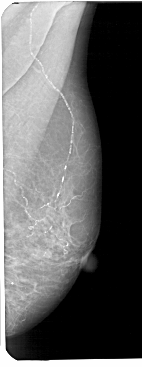

A_1191_1.LEFT_CC

LEFT_CC LINES 5071 PIXELS_PER_LINE 2356 BITS_PER_PIXEL 12 RESOLUTION 43.5 OVERLAY